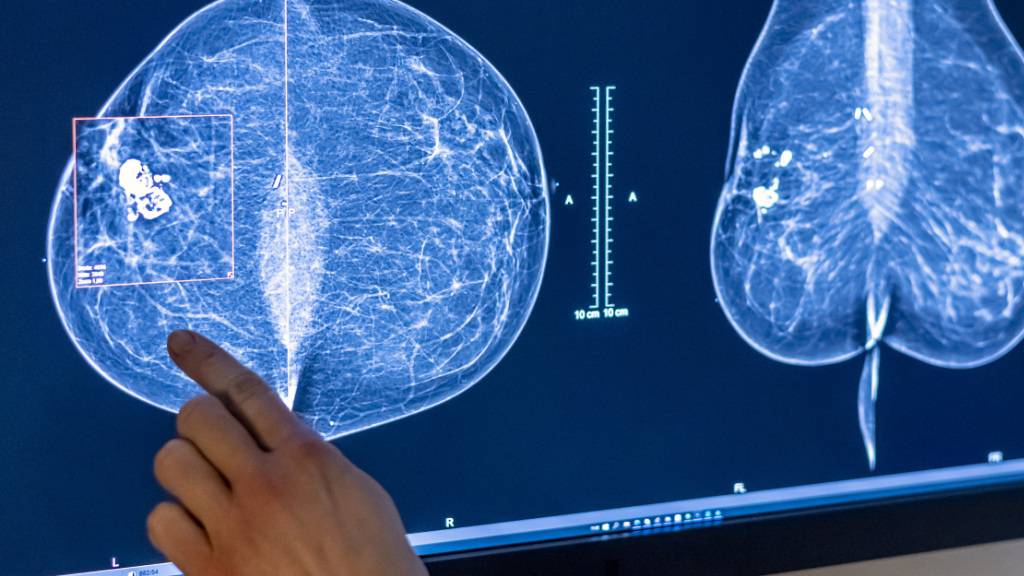

Eine neue Studie zeigt. wie gewisse Genvarianten teure Krebstherapien unwirksam machen können. (Archivbild)

Eine winzige Abweichung im Erbgut kann teure Krebsmedikamente nutzlos machen. Wie Forschende der Universität Basel in einer neuen Studie zeigen, können schon kleinste genetische Unterschiede die Wirksamkeit von Antikörper-Therapien aufheben.

Dies, indem sie die Bindung der Medikamente an ihr Ziel verhindern, wie eine am Mittwochabend in der Fachzeitschrift «Science Translational Medicine» erschienene Studie zeigt. Die Wissenschaftlerinnen und Wissenschaftler sehen in ihrer Entdeckung eine mögliche Erklärung, warum manche Patientinnen und Patienten nicht auf eine Antikörper-Therapie ansprechen.